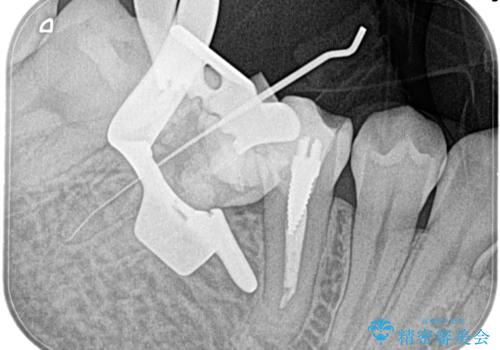

【湾曲根管】奥歯がズキズキ痛い

- 奥歯が1週間前からズキズキ痛いことを主訴に来院されました。

診査の結果、不可逆性歯髄炎と診断し抜髄処置を行っております。

- 精密根管治療(イニシャルケース,大臼歯):122,000円、ファイバーコア:22,000円費用は治療当時の料金となります

【使用ファイル】NEX-MS

【充填法】Hydraulic Condensation